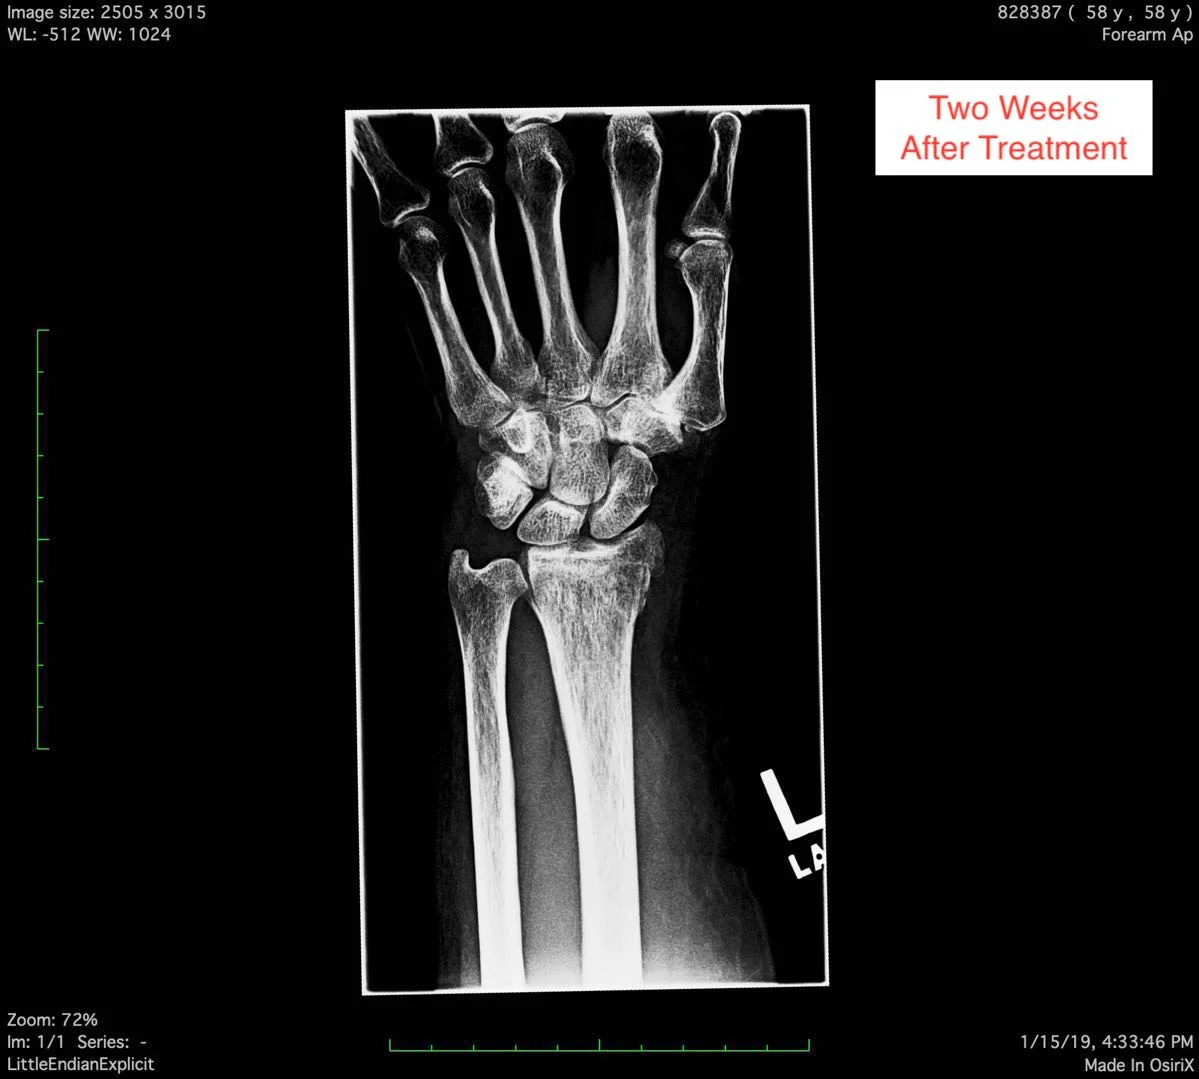

The fracture is Anti Coriolis fracture of the radial bone in the patient’s fore arm.

On this page, you can see the two X-ray pictures from before the treatment, showing the Anti Coriolis fracture of the radial bone. You can also see the X-ray pictures two weeks after the treatment, showing good bone alignment, and normal epiphyseal growth, indicating the clinical healing standard is reached.